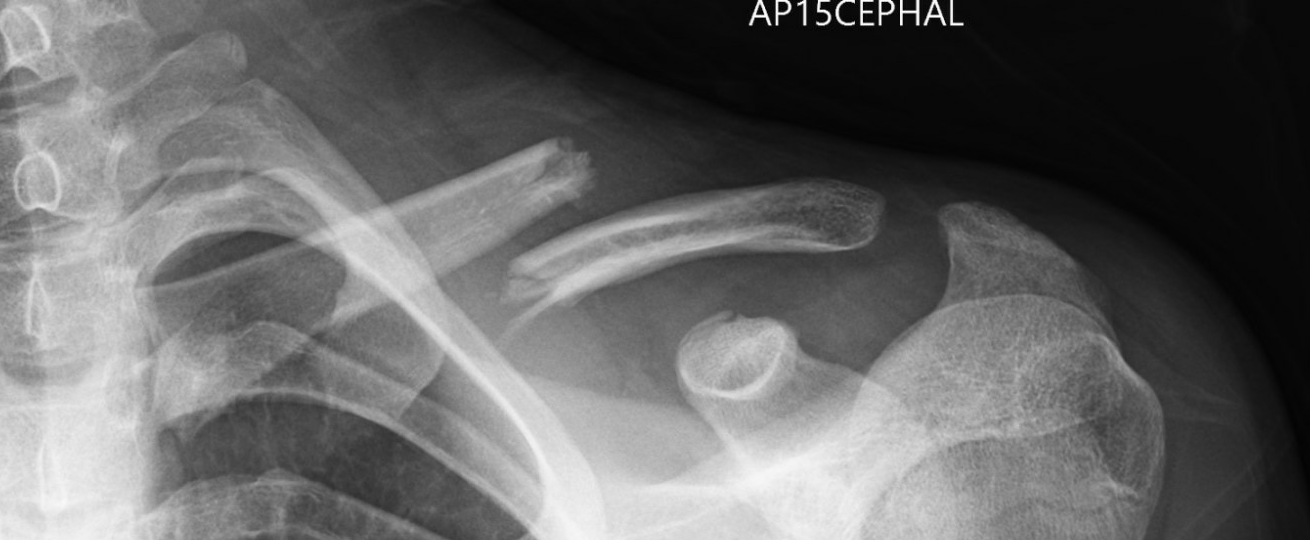

Some fractures are significantly displaced, like below.  In general these will usually require more aggressive treatment.

This is a “displaced” clavicle (collarbone) fracture. The fracture is also “shortened” as the ends of the bone are overlapping each other.